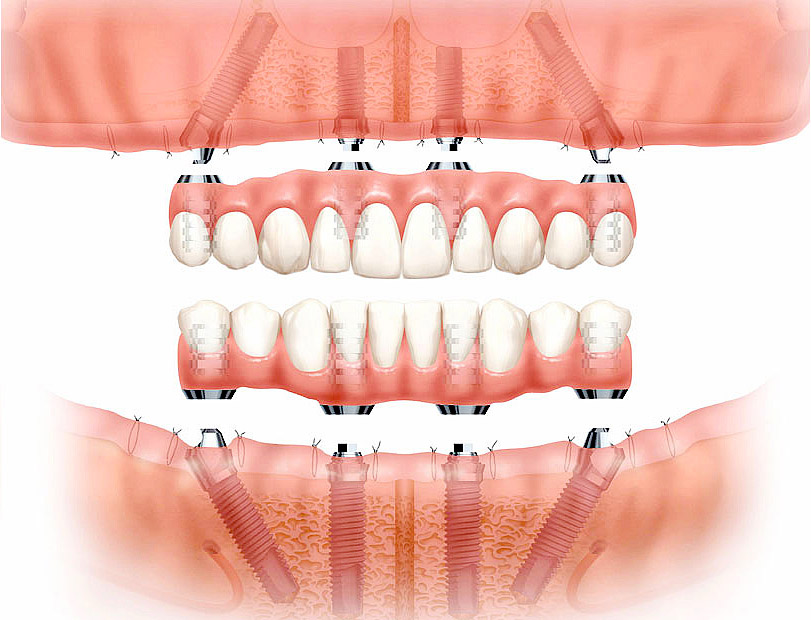

Visi ant 4 – viso bedančio žandikaulio dantų implantavimas ant 4 dantų implantų. Kauno klinika „Angitia“ šį originalų patentuotą švedišką metodą pradėjo taikyti viena pirmųjų Lietuvoje ir sėkmingai taiko iki šiol. Eilė implantų gamintojų šią idėją pradėjo realizuoti tik po kelių metų, visiškai įsitikinę neabejotina šios sistemos kokybe. Tačiau tik švediškųjų dantų implantų „Visi ant 4“ metodika yra geriausiai ištirta ir dokumentuota nuo 1990 m., o „Angitia“ klinikoje sėkmingai taikoma nuo 2006 m.

Ilgieji skruostikauliniai dantų implantai – operatyvus dantų implantavimo ir atkūrimo būdas sunykusiame viršutiniame žandikaulyje, pakeitęs sudėtingą kaulo priauginimo operaciją, bent pusmečiu sutrumpinęs implantavimo trukmę ir sumažinęs kainą. Ilgųjų dantų implantų unikali patentuota metodika pirmą kartą buvo pritaikyta 1990 m. Švedijoje, o klinikoje „Angitia“ – vienoje pirmųjų Pabaltijyje.

Tradiciniai, arba plokšteliniai, dantų protezai, tvirtinami dažniausiai ant 2 (dviejų) dantų implantų, – puikus ir patikimas sprendimas, nenumačiusiems implantuoti bedančio žandikaulių dantų. Pritvirtinti dantų protezai ant implantų, – skirtingai nuo fiksuojamų specialiais klijais, – laikosi stabiliai, netrina gomurio ir nesislankioja jokiomis kryptimis: pirmyn – atgal, aukštyn – žemyn ir į šonus. Dantų protezai ant implantų – palankus visų žandikaulio dantų atkūrimo sprendimas.